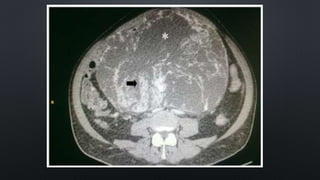

TAC: ideal para evaluar retroperitoneo

• Identificar los distintos componentes

• Diferentes coeficientes de absorción en tumor (liposarcoma)

GABINETE (3) TAC:ideal para evaluar retroperitoneo • Identificar los distintos componentes • Diferentes coeficientes de absorción en tumor (liposarcoma) RM: • Imágenes de gran nitidez • Mejor definición de los grandes vasos Biopsia • Aguja de tipo tru cut para muestra suficiente